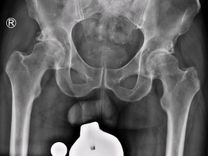

mein Name ist Prof. Hans Gollwitzer und ich heiße Sie auf meinem jameda-Profil ganz herzlich willkommen! Ich bin Facharzt für Orthopädie und Unfallchirurgie und Spezialist für Operationen an Hüfte und Knie sowie für die Arthrosebehandlung. Als Mitglied des kompetenten Ärzteteams von ECOM - Ihrer Praxis für Orthopädie, Sportmedizin, Unfallchirurgie und Endoprothetik in München bin ich auf den Kniegelenkersatz, den Hüftgelenkersatz und die Hüftarthroskopie spezialisiert. Unsere Philosophie lautet Exzellenz auf allen Ebenen: Wir stehen für exzellente Medizin, exzellenten Service und ein professionelles Netzwerk. Immer zum Wohle des Patienten.

In unserer Praxis verantworte ich als Spezialist die Implantation von Hüftprothesen und Knieprothesen, sowie das gesamte Spektrum der modernen gelenkerhaltenden Hüftchirurgie.

• die minimal-invasive und muskelschonende Hüftendoprothetik (AMIS Methode),

• bei Dysplasie und Fehlstellungen, bei Hüftkopfnekrose,